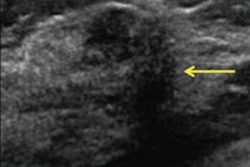

An MRI screening with a possible breast abnormality in the left breast (right side of the picture). Image courtesy of Carla van Gils, PhD."Although supplemental imaging increases the rate of cancer detection in women with dense breasts, the question remains whether it improves health outcomes," wrote lead author Marije Bakker, PhD, also from the Julius Center for Health Sciences and Primary Care, and colleagues.